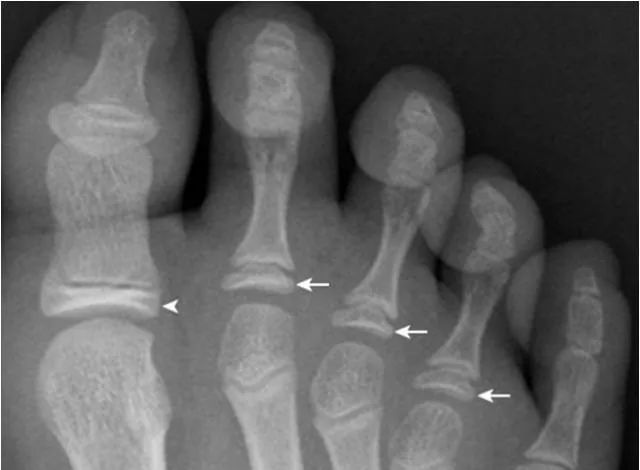

19.拇趾多分籽骨:

拇趾内外侧籽骨可表现为二分籽骨(箭)或三分籽骨(箭头),为正常变异,需与籽骨骨折、坏死鉴别。骨折边缘多不规则,坏死密度多不均。

21.足趾副骨:

趾跖关节内侧见点状骨性灶(箭),又称关节旁骨,一般无病理意义,但有时可引起邻近骨生长障碍和坏死。要与撕脱骨折鉴别。